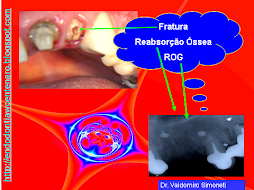

ENDO-OCLUSÃO

A ENDODONTIA PODE FRACASSAR SE A OCLUSÃO TIVER AJUSTADA

PELO DESGASTE APRESENTADO DA PARA IMAGINAR O QUE VAI ACONTECER!!!

SERÁ?

DOR!!!!!!!!!!!!!!!!!

É DA ENDO?

TINHA QUE DAR NISTO!!!!

E AGORA?